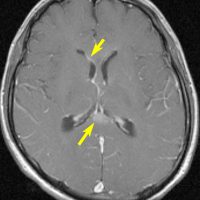

20歳くらいから尿崩症があり,2年後に汎下垂体機能低下症と軽度の認知機能低下を生じました。脳室壁と松果体,神経下垂体にジャーミノーマが広がっているのですが,脊髄背面と脳幹部の周囲にも腫瘍結節が見られました。脳室上衣以外の部位に腫瘍があるので,播種を疑いました。ジャーミノーマの播種というのは実際にはとても珍しくてなかなかみないものです。HCGは軽度の上昇,鼻孔から下垂体部分を生検して病理確定診断して,化学療法と脳脊髄照射 25.2Gy をしました。腫瘍は1コース目の化学療法でほとんど消失したので,他の組織型の悪性混合性胚細胞腫瘍ではないと考えられます。

3年後に脳室壁に再発しました。脳梁と脳弓の機能低下があり認知機能低下は高度でした。松果体と神経下垂体には再発はありません。

この再発の原因には,側脳室前角の先端部が照射野に十分含まれなかったという疑念があります。